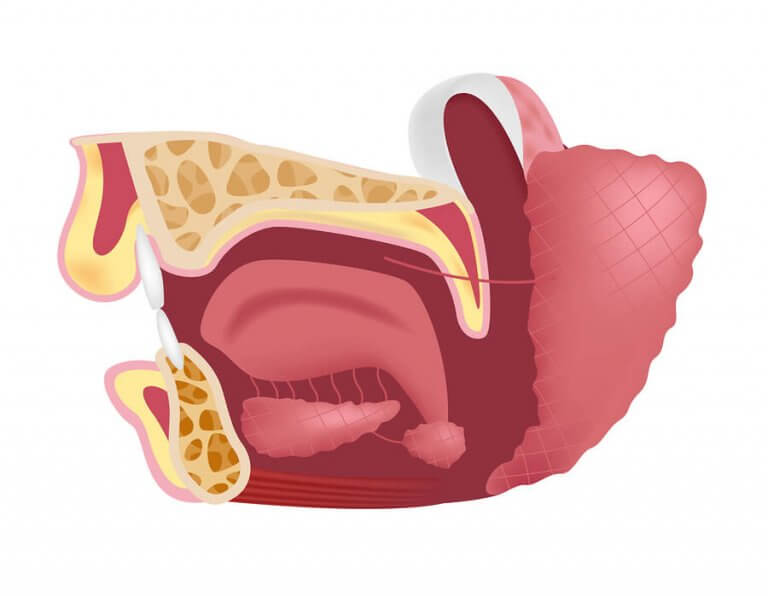

오늘은 턱밑샘의 기능에 대해 알아보자. 턱밑샘(submaxillary gland)은 악하선이라고도 하며, 구강 바닥 아래에 있는 두개골의 해부학적 위치로 인해 지어진 이름이다. 따라서 이는 턱밑샘, 귀밑샘, 혀밑샘으로 구성된 주된 침샘의 일부이다. 한쪽 뺨마다 귀 근처에 귀밑샘이 하나씩 있으며, 혀밑샘은 혀 아래에 있다.

턱밑샘은 결합 조직과 선 조직으로 구성되어 있으며, 장액 및 점액의 두 가지 유형의 선이 있다. 마찬가지로 결합 조직은 구조를 지탱하는 섬유를 포함하고 있다.

관은 턱밑샘에서 시작되며 타액을 구강에 흘러 들어가게 하는 기능이 있다. 턱밑샘관의 길이는 약 5cm이다.

턱밑샘관의 입구는 구강을 통해 맨눈으로 확인하고 촉진할 수 있다. 혀 주름띠의 양쪽에서 발견할 수 있다. 때로는 관이 막혔는지 여부를 확인하기 위해 치과 의사가 샘을 자극하여 타액이 분비될 수 있는지를 확인해야 한다.

혀 신경과 일부 얼굴 신경이 샘에 도달하여 타액 생성을 지시한다. 이는 구강 전체와 마찬가지로, 동맥과 정맥에 의해 관개되는 부위이다.